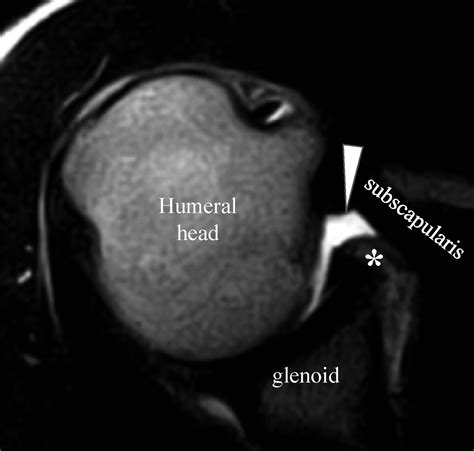

• Imaging Tests: X-rays, MRI, or ultrasound to visualize the joint and detect any abnormalities.

• glenohumeral joint effusion mri